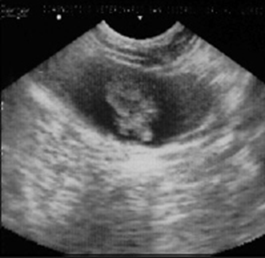

The cryosurgical option was suggested, but the owner declined. Four months later, during a follow-up ultrasound examination, an increase in the mass to 2.90 cm x 2.50 cm was confirmed (Figure 2). Faced with this situation, the owner agreed to the intervention.

Figure 2 Ultrasonographic diagnosis of bladder four months later: Increased mass measuring 2.90 cm x 2.50 cm.